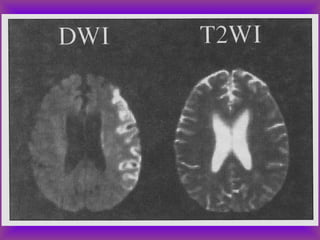

Diffuse Axonal (Shear) Injury (DAI)

Intra-axial Hemorrhage

T2: Reveals non-hemorrhagic lesions occult on CT

T2: Increased sensitivity to hemorrhage

• Tissues w/ differing elastic properties shear against each other,

tearing axons

• Caused by rapid deceleration/rotation of head

• Locations:

• Cerebral hemispheres near gray-white junction

• Basal ganglia

• Corpus callosum, especially splenium

• Dorsal brainstem

• High morbitity & mortality – common cause of post-traumatic

vegetative state

• Initial CT often normal despite poor GCS

• Lesions often non-hemorrhagic and seen only on MRI